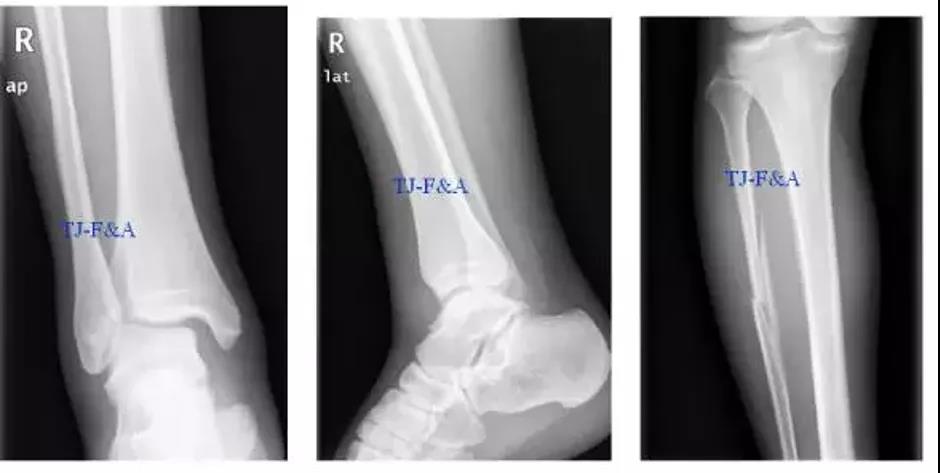

术前DR